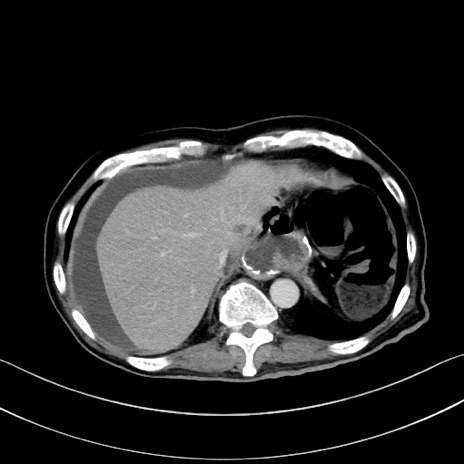

冠状断像

【症例】60歳代男性

【主訴】嘔吐

【現病歴】胃癌にて胃全摘後。食思不振が悪化し、夜中に嘔吐することがある。

【既往歴】胃癌、胃全摘、脾摘、胆摘後

【データ】WBC 5900、CRP 10.56